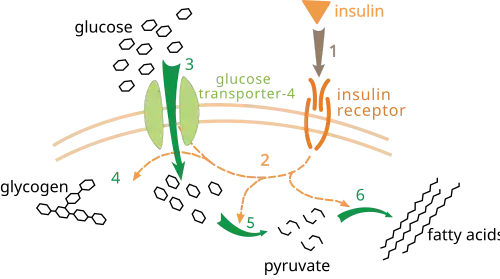

Glucose transporter type 4 (GLUT4), also known as solute carrier family 2, facilitated glucose transporter member 4, is a protein encoded, in humans, by the SLC2A4 gene. GLUT4 is the insulin-regulated glucose transporter found primarily in adipose tissues and striated muscle (skeletal and cardiac). GLUT4 is distinctive because it is predominantly stored within intracellular vesicles, highlighting the importance of its trafficking and regulation as a central area of research.[5] The first evidence for this glucose transport protein was provided by David James in 1988.[6] The gene that encodes GLUT4 was cloned[7][8] and mapped in 1989.[9]

At the cell surface, GLUT4 permits the facilitated diffusion of circulating glucose down its concentration gradient into muscle and fat cells. Once within cells, glucose is rapidly phosphorylated by glucokinase in the liver and hexokinase in other tissues to form glucose-6-phosphate, which then enters glycolysis or is polymerized into glycogen. Glucose-6-phosphate cannot diffuse back out of cells, which also serves to maintain the concentration gradient for glucose to passively enter cells.[10]

Insulin is released from the pancreas and into the bloodstream in response to increased glucose concentration in the blood.[26] Insulin is stored in beta cells in the pancreas. When glucose in the blood binds to glucose receptors on the beta cell membrane, a signal cascade is initiated inside the cell that results in insulin stored in vesicles in these cells being released into the blood stream.[27] Increased insulin levels cause the uptake of glucose into the cells. GLUT4 is stored in the cell in transport vesicles, and is quickly incorporated into the plasma membrane of the cell when insulin binds to membrane receptors.[24]

Under conditions of low insulin, most GLUT4 is sequestered in intracellular vesicles in muscle and fat cells. As the vesicles fuse with the plasma membrane, GLUT4 transporters are inserted and become available for transporting glucose, and glucose absorption increases.[28] The genetically engineered muscle insulin receptor knock‐out (MIRKO) mouse was designed to be insensitive to glucose uptake caused by insulin, meaning that GLUT4 is absent. Mice with diabetes or fasting hyperglycemia, however, were found to be immune to the negative effects of the insensitivity.[29]

The mechanism for GLUT4 is an example of a cascade effect, where binding of a ligand to a membrane receptor amplifies the signal and causes a cellular response. In this case, insulin binds to the insulin receptor in its dimeric form and activates the receptor's tyrosine-kinase domain. The receptor then recruits Insulin Receptor Substrate, or IRS-1, which binds the enzyme PI-3 kinase. PI-3 kinase converts the membrane lipid PIP2 to PIP3. PIP3 is specifically recognized by PKB (protein kinase B) and by PDK1, which can phosphorylate and activate PKB. Once phosphorylated, PKB is in its active form and phosphorylates TBC1D4, which inhibits the GTPase-activating domain associated with TBC1D4, allowing for Rab protein to change from its GDP to GTP bound state. Inhibition of the GTPase-activating domain leaves proteins next in the cascade in their active form, and stimulates GLUT4 to be expressed on the plasma membrane.[30]